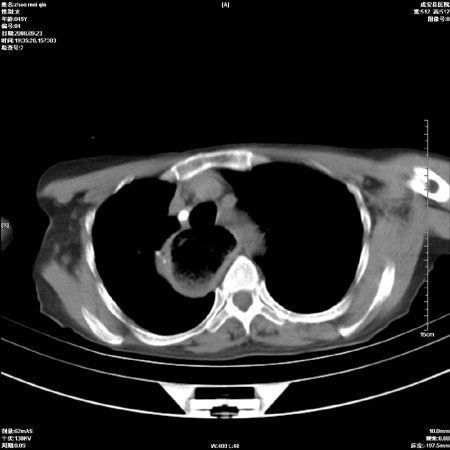

外伤后1小时 胸疼 是外伤后引起的吗?

食道扩张明显下端逐渐变窄,倒像贲门失迟缓

未除外食道异物。如食道石长时间受阻。

考虑术后改变(胸腔胃),建议询问病史.

非外伤性改变,典型的贲门失迟缓症

食道扩张明显下端逐渐变窄,大量食物存留,象贲门失迟缓症。